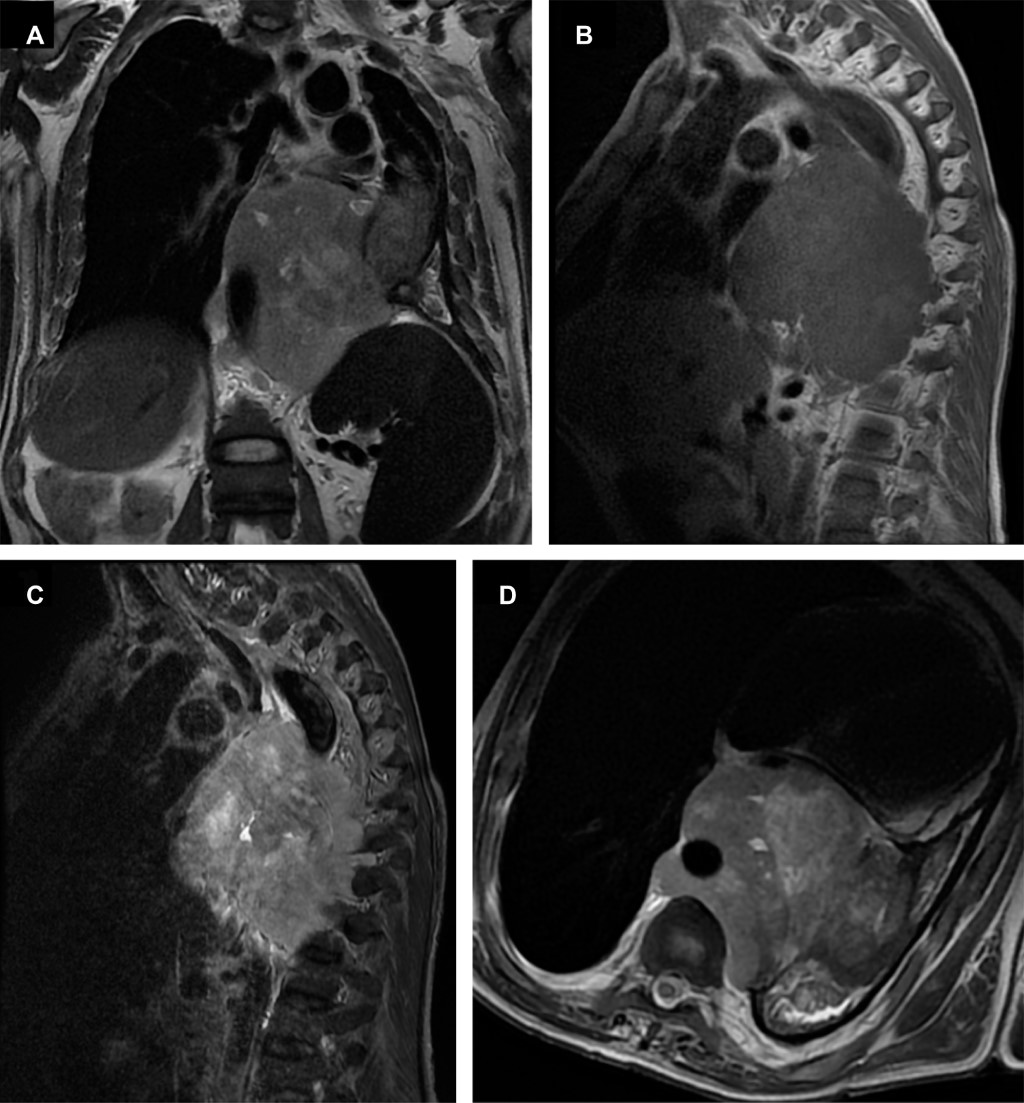

Hombre de 40 años, con dolor en región dorsal de un mes de evolución secundario a cargar objeto pesado, con antecedente de escoliosis secundaria a insuficiencia renal crónica desde hace 10 años y trasplantado renal hace cuatro años, acude para valoración con resonancia magnética de región dorsal (Figura 1).

Los estudios de imagen comúnmente realizados son la tomografía computada, ya que permite delimitar la invasión, visualizar calcificaciones; y la resonancia magnética, esta última mostrando un mejor rendimiento diagnóstico. En la RM la presentación típica de los schwannomas es una lesión adyacente al trayecto nervioso, de comportamiento iso-hipointenso en T1, hiperintenso en T2 y realce posterior al contraste. La intensidad de la señal heterogénea y el realce posterior al contraste sugieren una hemorragia interna y cambios quísticos.3 De acuerdo con la bibliografía consultada, la resección quirúrgica, ya sea por técnica mínimamente invasiva o abierta, resulta el tratamiento de elección para esta patología, mismo que requiere de una buena planeación quirúrgica derivada de estudios de imagen.1

Figura 1